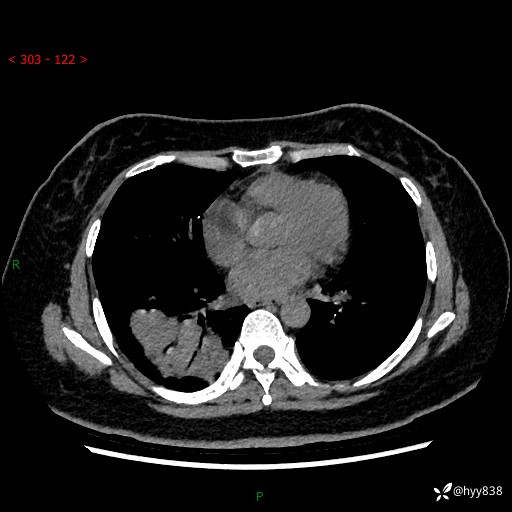

增强动脉期+静脉期